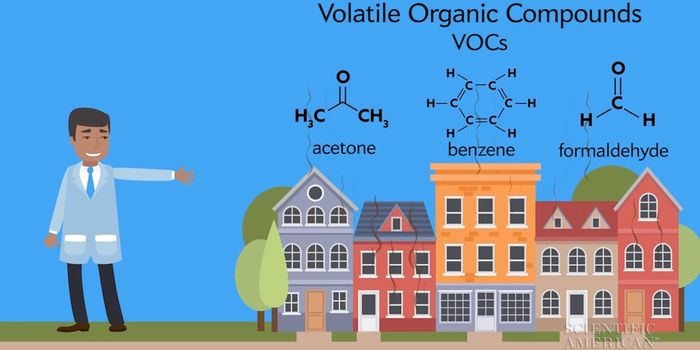

DEC 05, 2017VideosAccording to new research, five chemicals used in the process of fracking are linked to permanent brain damage, particul ...